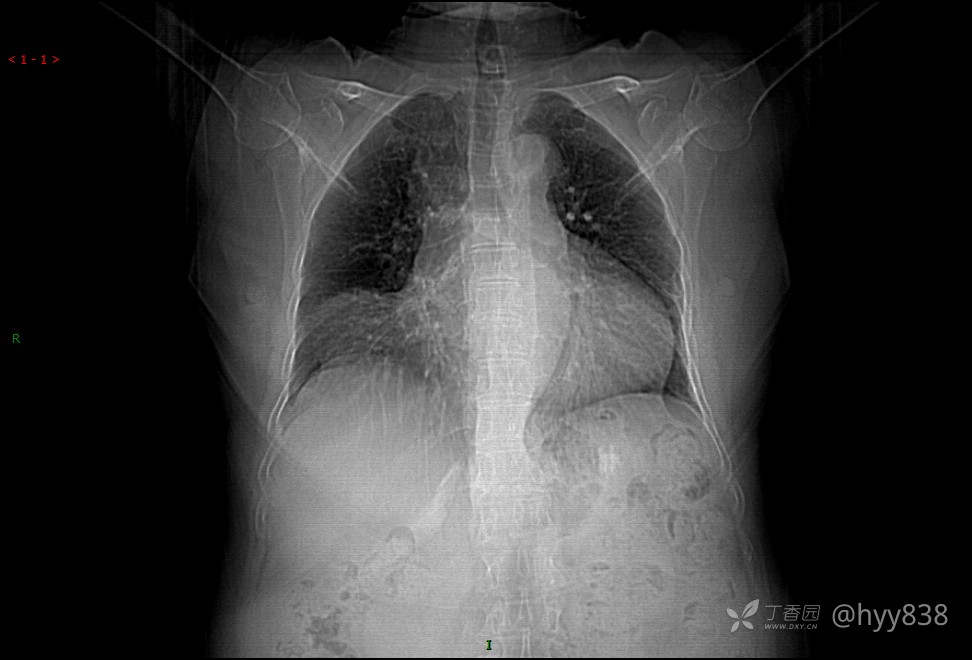

一张胸片让病人惊出一身冷汗,连夜到上级医院确诊,what happened? 结果公布~

患者性别:男

患者年龄:76岁

简要病史:健康体检发现右下肺占位

辅助检查:平片 CT

讨论:病变性质?

胸片